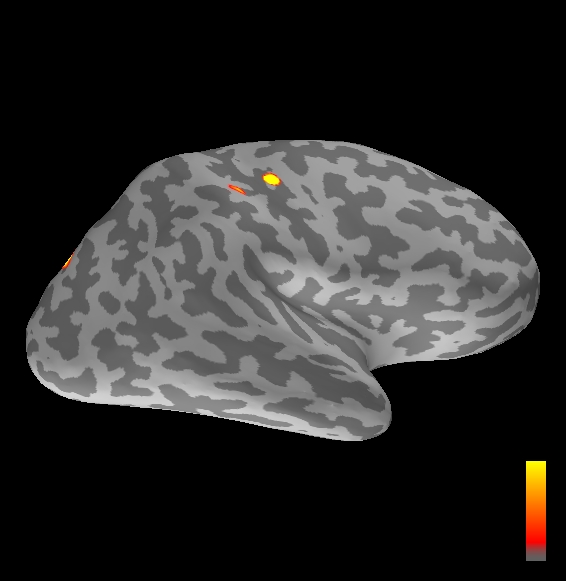

5.2 Results

We applied the ASMC sampler to MEG topographies taken from the above recordings by selecting specific time points according to the previous analysis; the parameter values in the algorithm were the same as those used for the analysis of synthetic data, with the only exception of the noise standard deviation , here estimated from the pre–stimulus interval. In order to validate the results of the ASMC, we also computed source estimates using three other methods: a PF, that approximates the posterior distribution for the current dipoles conditioned on the data up to the selected time point; dSPM, which is based on a distributed source model with an –prior, and consists in normalizing the Tikhonov regularized solution by the noise standard deviation; and sLORETA, which is similar to dSPM but is claimed to have a smaller localization bias. Figure 4 shows the results at , and ms after the stimulus onset. The results are visualized on a computer representation of the brain obtained by “inflating” the cortical surface: gray levels contain the anatomical information, light gray representing gyri and dark gray representing sulci; the activity estimate is coded in color scale, increasing from red to yellow. Importantly, this visualization allows activity in the sulci to be clearly visible; on the other hand, since neighbouring volumes may be moved apart by the inflation process, distinct activity regions are often due to underlying volumetric masses that are very close to each other.

Before describing the results, let us comment on the qualitative difference between the images produced by the ASMC sampler and the PF, on the one hand, and those produced by dSPM and sLORETA, on the other. First of all, we point out that all the quantities shown in the images of Fig. 4 are somehow related to the probability of activation at specific locations. Indeed, for both the ASMC and the PF we plot the approximation of the intensity measure (3.8); for any single grid point, this value can be interpreted as the probability of a dipole being at that location, while it integrates, over a given volume , to the mean number of dipoles within . As for dSPM, the represented quantity is a statistical value that is –distributed under the null–hypothesis of zero activity; as a direct consequence, it also yields a probability of activation, which is however not constrained to be dipolar. Similar considerations apply to sLORETA, although with a different statistical distribution. Importantly, the representation of the results is clearly affected by the setting of the visualization threshold. Owing to the explained differences between the methods, it seems reasonable to use a different value for each method. At the same time, since the plotted quantity is a probability of activation, it seems right to use the same thresholding for different time points. In this connection, the thresholds in Fig. 4 have been chosen by hand following the guidelines just outlined.

Using the same thresholding and parameters at different time points makes the four methods respond differently to the diverse intensities of the different sources. Whenever a stronger source is active, both sLORETA and dSPM will tend to produce widespread estimates, while weaker sources will be represented as small active areas. The behaviour of the ASMC and of the PF is the opposite: a stronger signal will lead to a precise localization of a dipolar source, and then to a focal marginal distribution for the location; a weaker signal will translate to higher uncertainty on the source position, and therefore a more widespread posterior map.

The phenomenon just described is indeed clearly visible in Figure 4. At ms, all the methods correctly identify the rather strong activation in the contra–lateral primary somatosensory cortex: the ASMC and the PF provide very focal maps, while dSPM and sLORETA provide compatible widespread estimates; dSPM also exhibits a more posterior peak which does not fit with the commonly agreed models of the response to median nerve stimulation; this may be due to the formerly described brain inflation.

At ms, the ASMC localizes two sources, one in the right hemisphere and a weaker one in the left hemisphere; these sources appear to be compatible, for timing and location, with the Posterior Parietal Contra and Parietal Opercular Ipsi described in Mauguiere et al. (1997). The PF finds the very same source in the right hemisphere, but it estimates no dipoles in the left one. Such discrepancy between these two methods, which are based on the same source model, is possibly due to two facts: first, thanks to its iterative nature, the ASMC is likely to explore the state space more thoroughly and is therefore more suited to identify weak sources; second, the log–uniform prior on the strength of the dipole moment in the ASMC has a wider range than the corresponding Gaussian prior in the PF. Slightly different results are provided here by dSPM and sLORETA. The activity estimate computed by dSPM seems very similar to that of ms, having the same spatial distribution with a weaker intensity. The estimate of sLORETA in the right hemisphere includes that of the ASMC and of the PF. Neither dSPM nor sLORETA find significant activity in the left hemisphere.

At ms, the ASMC localizes again two sources: a stronger one in the right primary somatosensory cortex, and a weaker one in the left posterior frontal area. Both of them seem to be compatible, for timing and location, with the results in Mauguiere et al. (1997), the left dipole corresponding to the Frontal Ipsi source. Once again, the other three methods only recover the stronger source.